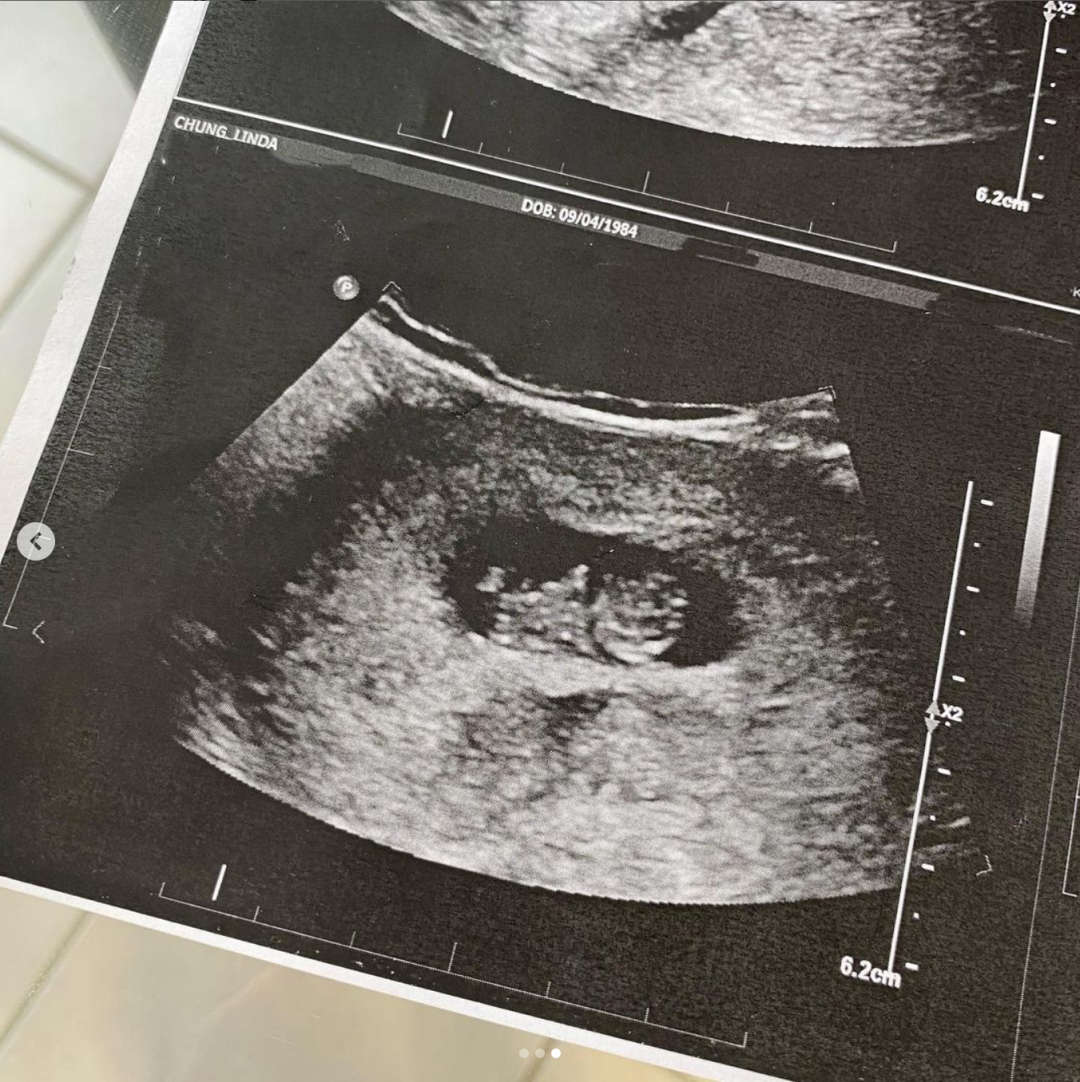

钟嘉欣分享了自己的B超单,一个鲜活的小生命即将到来,全家人都期待不已。

在最后一张照片里,钟嘉欣放大了一张B超,可以看到在钟嘉欣的肚子里,孩子已经初具雏形,能明显看出头和身子,但两只小手和小脚都还比较模糊。

不过这次,钟嘉欣并未透露孩子的性别,看来大家有得一猜了。